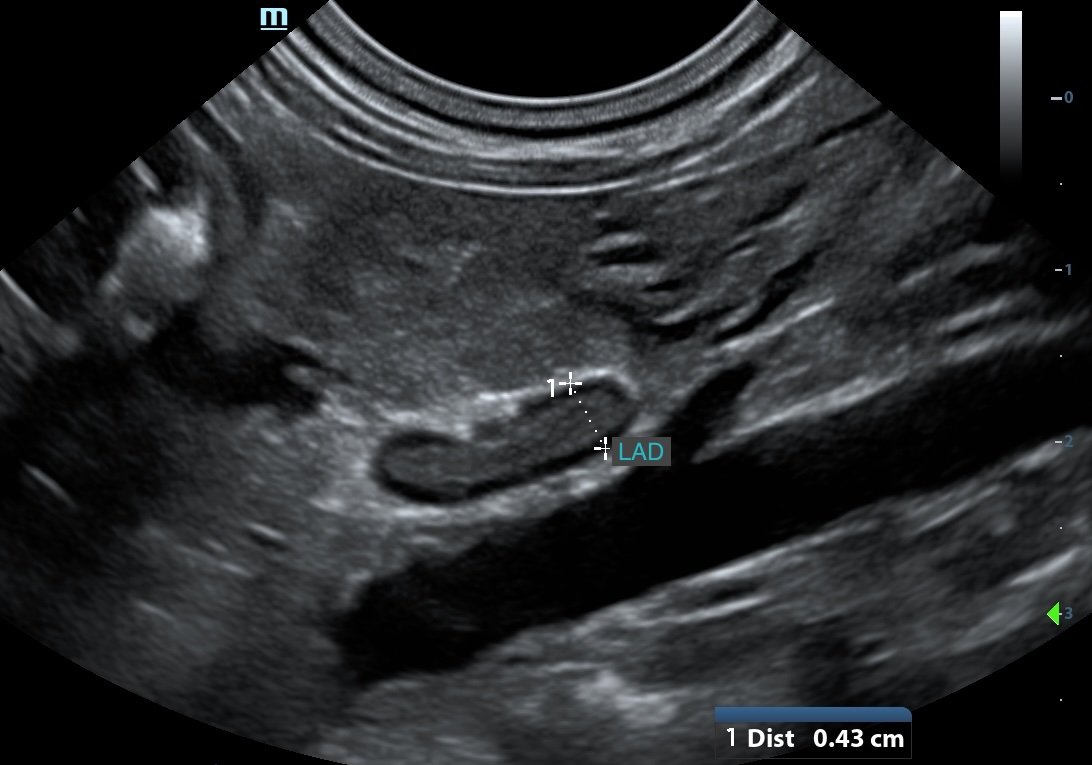

WATCH HOW IT ACTUALLY CAN LOOK IN PRACTICE

• reliably locate adrenal glands using consistent anatomical landmarks

• recognise normal vs abnormal with more confidence

• handle small or difficult-to-find adrenals